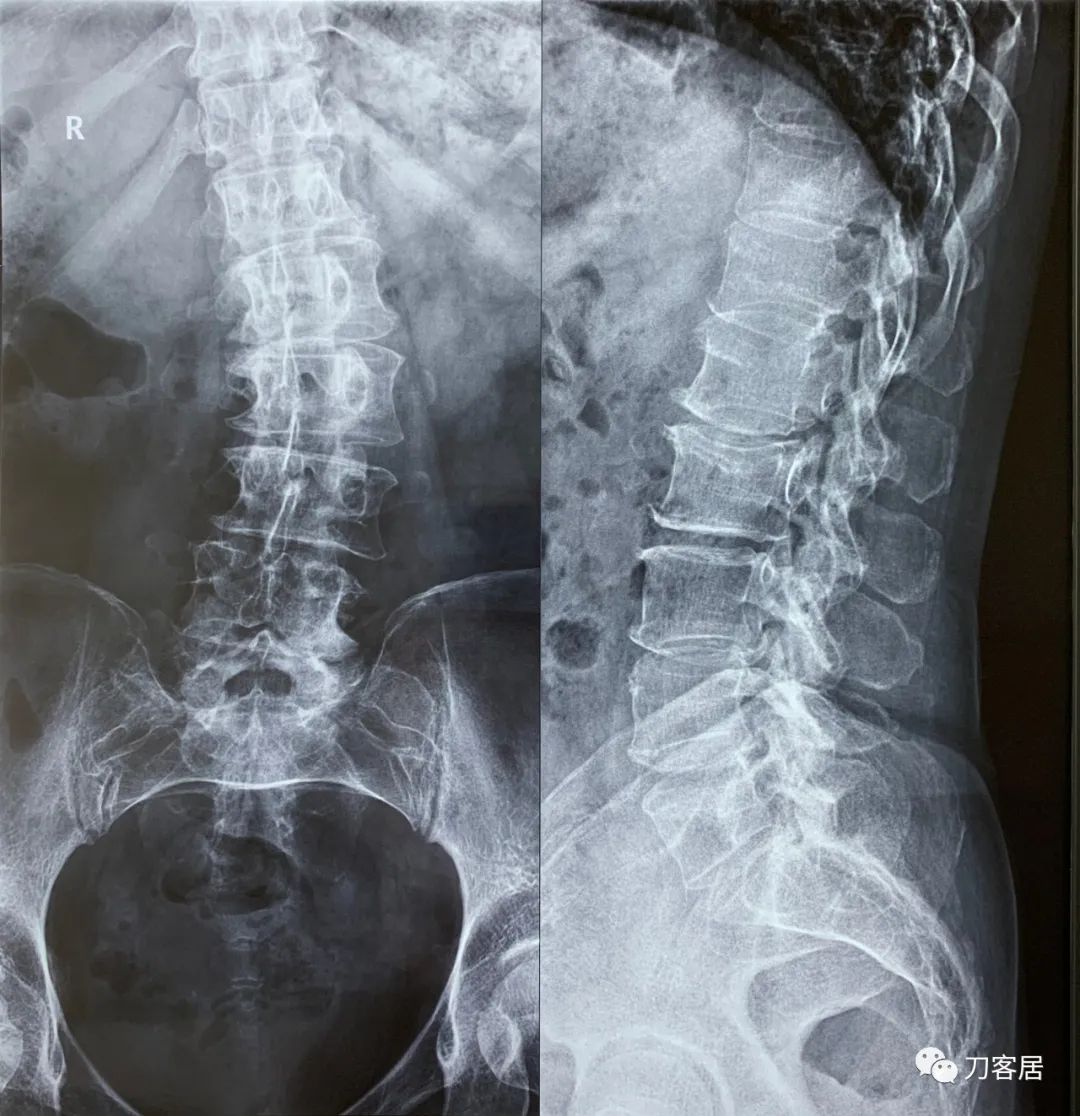

建议其查双光子骨密度,骨盆正位片以及腰椎间盘平扫。腰椎正侧位X线片以及动力位片,站立位脊柱全长正侧位X线片,以了解其是否有骨质疏松,并了解脊柱侧弯情况,腰椎局部X线表现情况和腰椎间盘突出和椎管狭窄情况。

从这个患者的影像资料分析,颈椎间盘突出问题不大,没有明确的上位神经元损伤表现,所以,不考虑颈椎和胸椎问题。腰椎侧弯畸形,但不严重。因为存在腰椎侧弯,使得腰椎MRI在扫描切面的时候,显示的椎间盘突出或椎管狭窄会有一定的误差,所以,又加做了经椎间盘的CT平扫,影像表现并不严重,综上,腰椎间盘突出,腰椎管狭窄,腰椎侧弯,不考虑手术治疗。同时,患者的主要痛苦是心理疾病,而不是器质性疾病,所以,以心身疾病治疗为主。虽然患者骨密度检查结果提示正常,但X线片显示骨质疏松,且其症状也与骨质疏松的症状有符合之处,比如静息痛,不能入睡,动作及姿势变换时痛加重等,所以,给予实验性抗骨质疏松治疗,以观疗效。